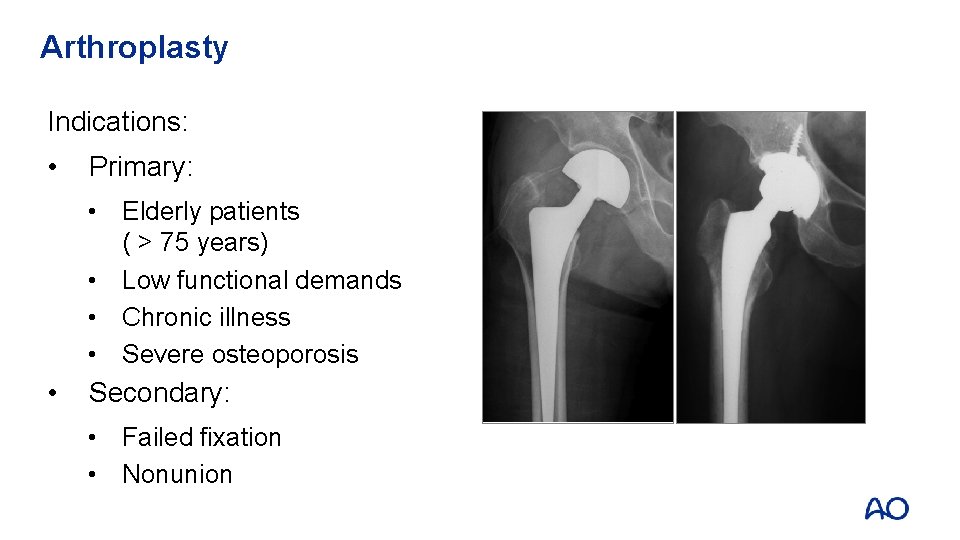

Arthroplasty Indications: • Primary: • Elderly patients ( > 75 years) • Low functional demands • Chronic illness • Severe osteoporosis • Secondary: • Failed fixation • Nonunion

Arthroplasty Advantages: • Allows immediate weight bearing • Eliminate AVN and nonunion • Significantly reduces the incidence of reoperation

Arthroplasty Disadvantages: • Greater infection rates • More blood loss and longer operative time • Possible increase in early mortality rates